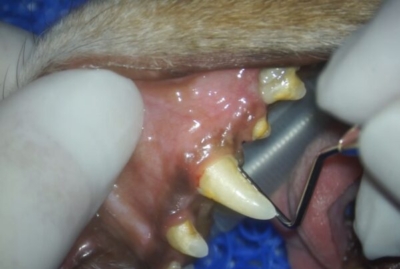

歯科レントゲンの次は、プロービングといって歯周ポケットの深さや動揺の有無、根っこの分岐が見えてしまっていないかなどのチェックをします。

右犬歯の手前に5mmの歯周ポケット

奥には10mmの深い歯周ポケット

小型犬の健康な歯周ポケットは3mmまででしょうから、かなり深いポケットです。上顎犬歯は左右とも同様の深いポケットで鼻腔とつながっており基礎疾患と年齢から、残念ながら抜歯を選択しました。口腔鼻腔ろうはこのままですと、くしゃみや鼻水、食欲不振、最悪肺炎まで起こしかねません。

歯肉を切開すると骨がほとんどありませんでした

抜歯し、膿や肉芽を切除。奥に鼻腔が見える